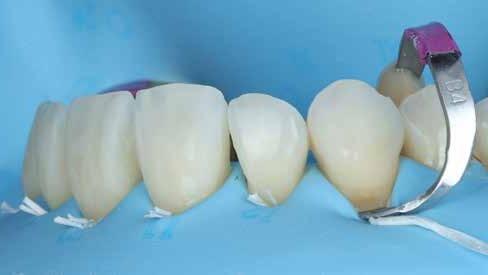

Eltávolításra került a retenciós drót, valamint az összes korábbi kompozit restauráció (6–9. ábra). Ezt követően kofferdam izolálást alkalmaztunk (Isodam Heavy, Sigma Dental) a 15-östől a 25-ös fogig, majd PTFE fonalból készült ligatúrákat (Tandex) helyeztünk be az íny hatékonyabb retrakciója érdekében (10. ábra). A 13-as fognál egy további kofferdam kapocs (Brinker B4, Coltene) is felhelyezésre került, hogy fokozott retrakciót biztosítson, és megfelelően izolálja az ínyrecessziót. A kapocs ívét önsavazó folyékony kompozit-

tal rögzítették (11. ábra). Minden fogat alaposan homokfúvott 29 μm-es alumínium-oxiddal (Aquacare Twin, Velopex), majd 37%-os foszforsavval savazott. Ezt követően minden fogon primer és bonding került felvitelre, majd a 13-as fog restaurálására a G-ænial A’CHORD A1 árnyalatot alkalmazta (12. ábra). Ezután a 12-es fog meziális felszínén történt rest-

10. ábra: Kofferdam izolálás. A fogselyem ligatúrákkal további retrakció érhető el.

12. ábra: A 13-as fog cervikális restaurációja után.

auráció, majd sorra kerültek a 11-es és 21-es fogak. Diasztémák vagy fekete háromszögek zárásakor kiemelten fontos a precíz cervikális kapcsolat kialakítása, miközben mindkét fogegységet egyenletesen kell szélesíteni. Mivel a cervikális és incizális terület között jelentős távolság volt, egy kis „dudor” alakult ki, mielőtt a fog többi részét felépítette vol-

13-16. ábrák: Először egy kis „domborulat” készült átlátszó matrica segítségével; 14) Ez a „domborulat” mindkét fogon kialakításra került, mielőtt a fekete háromszög többi részét lezárták. Ez a módszer nagyobb kontrollt biztosít a restauráció kontúrja és a végső szimmetria felett. 15) Mindkét „domborulat” kialakítása után. 16) A 21-es fog befejezése után. – 17. ábra: Szimmetrikus eredmény mindkét metszőfog befejezése után. – 18–19. ábra: A 12-es és 22-es fogakat tovább bővítették, hogy (nagy részben) lezárják a fekete háromszögeket. – 20. ábra: A kompozitot a fogak bukkális felszínétől egészen a palatinális oldalig lett applikálva a szélesítés érdekében. Ez egyben biztosítja az íny megfelelő megtámasztását is. – 21. ábra: Új retenciós drót elhelyezése. – 22. ábra: Közvetlenül a kofferdam eltávolítása után.

na. Ehhez előre formázott csíkot alkalmazott (BlueView VariStrip, Garrison) (13–14. kép). A dudorok kialakítása után a csíkot eltávolította (15. kép). Ebben a fázisban, szükség esetén, polírozással lehet finomítani, például a tér elosztásának javítása érdekében. Ezután a csíkot visszahelyezte, és a 21es fog incizális éle és a kidudorodás közötti rést kompozit anyaggal töltötte fel (16. ábra). Ezt követően a 11-es fogat is felépítette (17. ábra). Ezt követően a 22-es fog került sorra. Miután minden elemet felépített, gondosan magasfényűre polírozta őket (Diacomp Plus Twist, EvE), majd az összes proximális érintkezést ellenőrizte fogselyemmel (18–20. ábra). Ezután új retenciós sín került felhelyezésre (21. ábra). Közvetlenül a beavatkozás után mindig megfigyelhető egy fekete háromszög, mivel a kofferdam visszahúzta az ínyt.